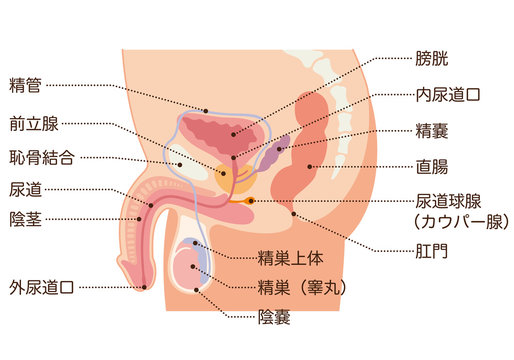

男性生殖器 断面図のイラスト素材

男性生殖器断面人体図 名称付き メディカルイラスト図鑑 無料の医療 美容素材集

男性生殖器断面人体図 名称付き メディカルイラスト図鑑 無料の医療 美容素材集

男性生殖器 断面図 Stock Illustration Adobe Stock

男性生殖器 断面図のイラスト素材

男性生殖器 断面図のイラスト素材

人体模型 男性骨盤 正中断面模型